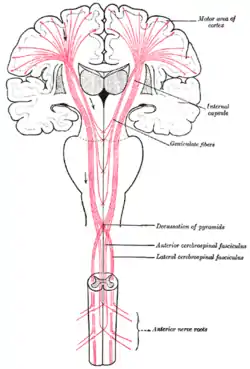

Pathway

As the primary motor axons travel down through the cerebral white matter, they move closer together and form part of the posterior limb of the internal capsule.

They continue down into the brainstem, where some of them, after crossing over to the contralateral side, distribute to the cranial nerve motor nuclei. (Note: a few motor fibers synapse with lower motor neurons on the same side of the brainstem).

After crossing over to the contralateral side in the medulla oblongata (pyramidal decussation), the axons travel down the spinal cord as the lateral corticospinal tract.

Fibers that do not cross over in the brainstem travel down the separate ventral corticospinal tract, and most of them cross over to the contralateral side in the spinal cord, shortly before reaching the lower motor neurons. In addition to the main corticospinal tract, Motor cortex projects to other cortical and subcortical areas, including the striatum, hypothalamus, midbrain and hindbrain, as well as the thalamus, basal ganglia, midbrain and medulla[4]

The motor tract.

The motor tract.